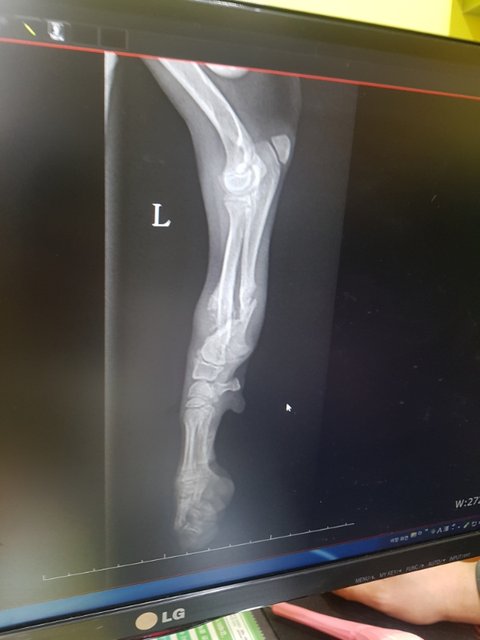

보호소 입소때부터 앞다리를 들고 있었고 조금씩 딛고 있는 모습에 설마 골절은 아니꺼라 생각했습니다.

앞다리는 골절 거기다 코로나에 걸렸습니다.